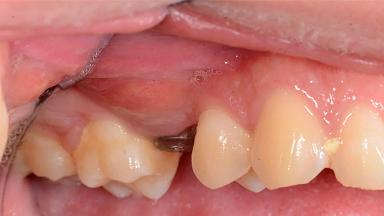

Management of a Fractured Implant Supporting a Screw-retained Metal-ceramic Restoration

The fracture of an implant after it has been restored is one of the most severe complications. It most frequently occurs in partially edentulous jaws (1.5%). Most implant fractures involve implants with a diameter of 3.75 mm made of commercially pure titanium (Eckert 2010). Unfortunately, many cases are not reported or documented by the clinicians involved in resolving the problems created by the fracture. This case report describes the management of an implant fracture at site 36 in a middle-aged male patient. The implant had been restored with a screw-retained metal-ceramic crown.